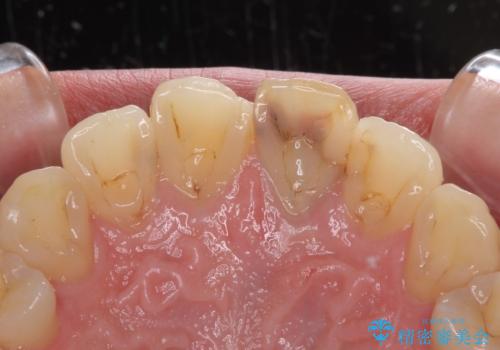

- 前歯が変色してしまったとのことで来院された患者様です。

変色が気になっていたものの痛みがなかったので看過していましたが、歯肉が腫れることが頻回となったため来院されました。

歯髄は既に壊死していたため、根管治療を行い、その後オールセラミッククラウンにて補綴することとしました。